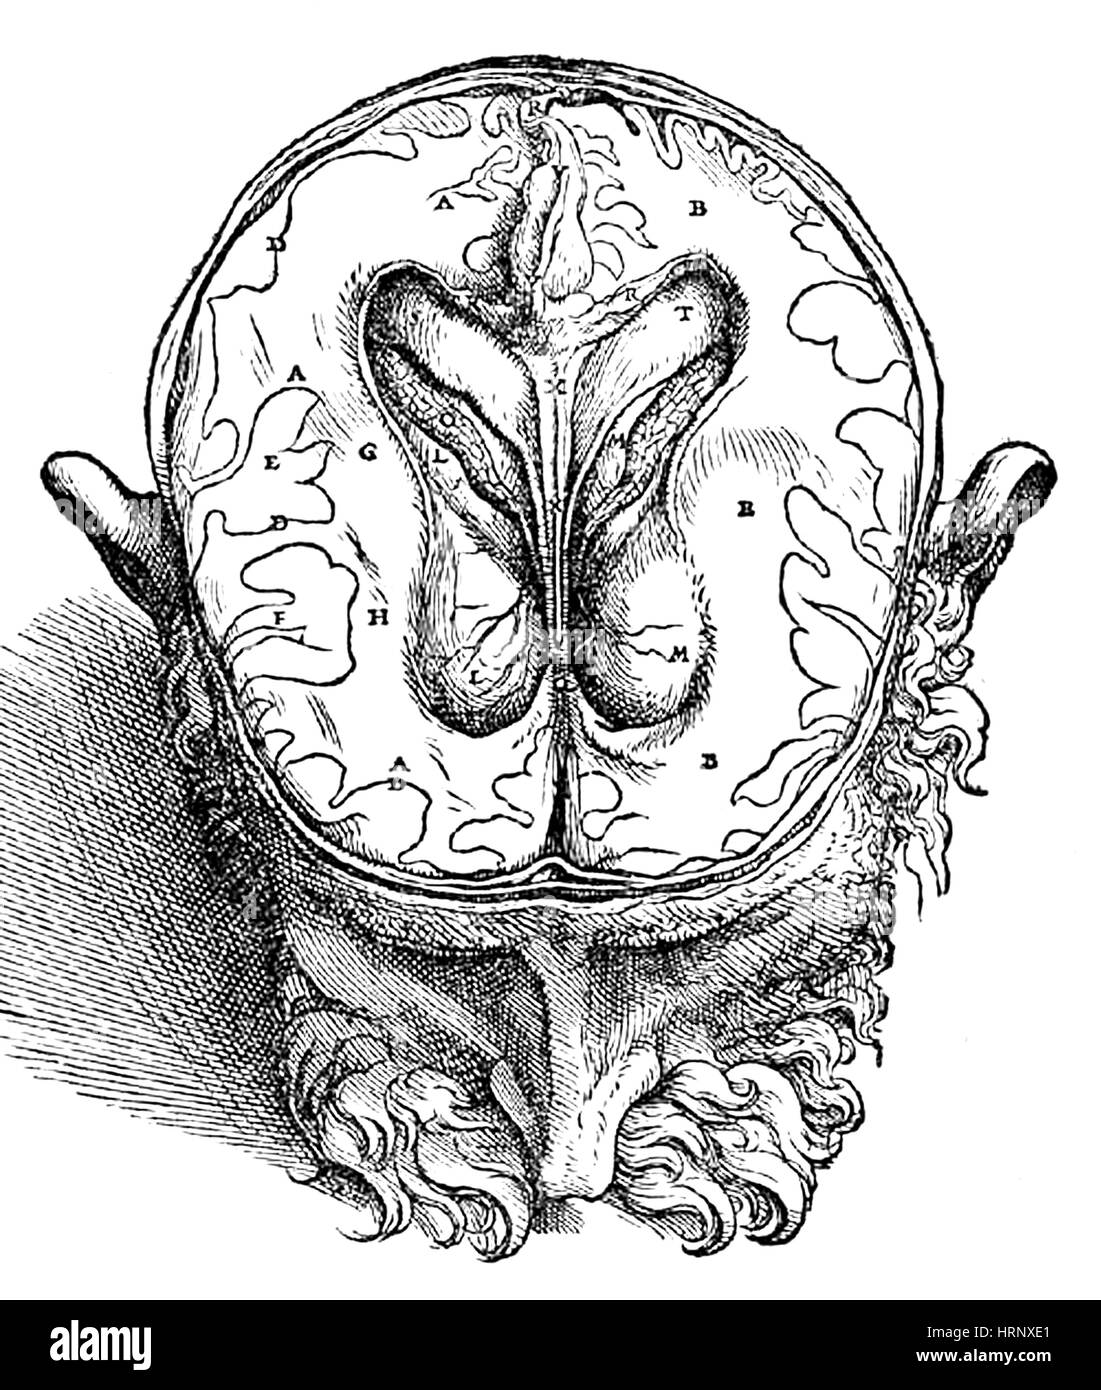

Human Brain, Vesalius, 16th Century Stock Photohttps://www.alamy.com/image-license-details/?v=1https://www.alamy.com/stock-photo-human-brain-vesalius-16th-century-135091433.html

Human Brain, Vesalius, 16th Century Stock Photohttps://www.alamy.com/image-license-details/?v=1https://www.alamy.com/stock-photo-human-brain-vesalius-16th-century-135091433.htmlRMHRNXE1–Human Brain, Vesalius, 16th Century

Human Brain, Vesalius, 16th Century Stock Photohttps://www.alamy.com/image-license-details/?v=1https://www.alamy.com/stock-photo-human-brain-vesalius-16th-century-135091430.html

Human Brain, Vesalius, 16th Century Stock Photohttps://www.alamy.com/image-license-details/?v=1https://www.alamy.com/stock-photo-human-brain-vesalius-16th-century-135091430.htmlRMHRNXDX–Human Brain, Vesalius, 16th Century

Human Brain, Vesalius, 16th Century Stock Photohttps://www.alamy.com/image-license-details/?v=1https://www.alamy.com/stock-photo-human-brain-vesalius-16th-century-135091431.html

Human Brain, Vesalius, 16th Century Stock Photohttps://www.alamy.com/image-license-details/?v=1https://www.alamy.com/stock-photo-human-brain-vesalius-16th-century-135091431.htmlRMHRNXDY–Human Brain, Vesalius, 16th Century